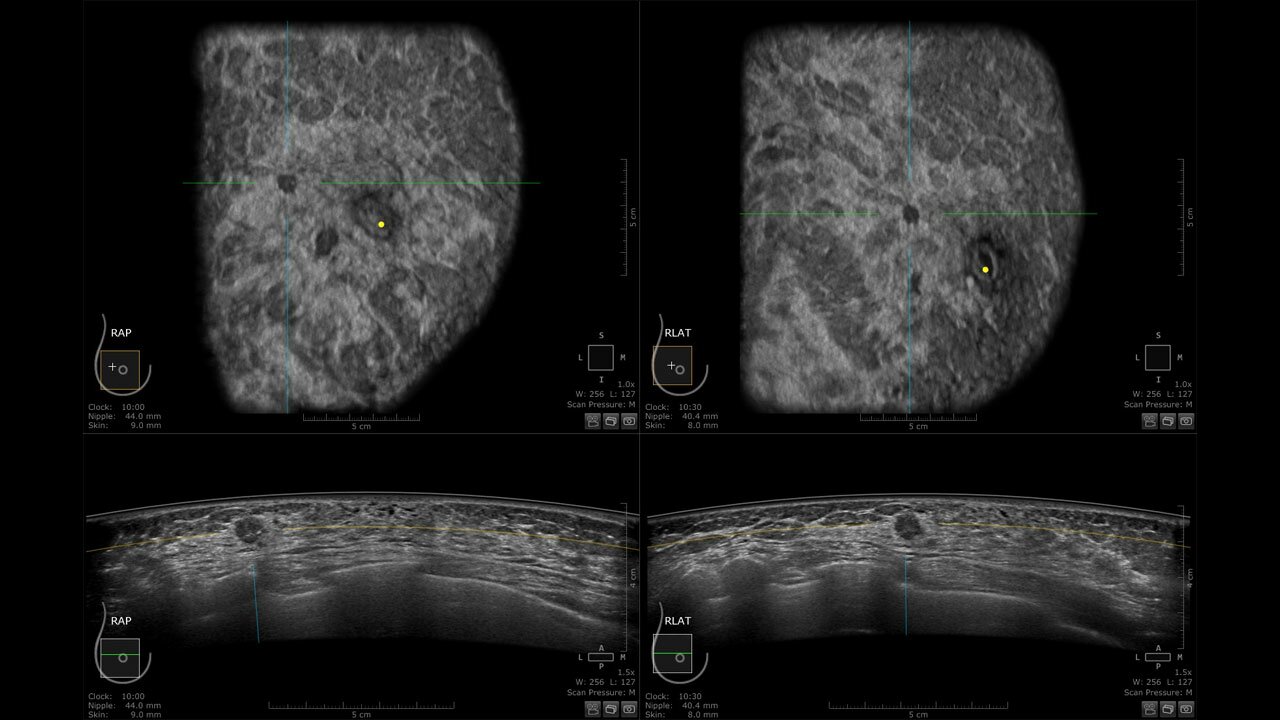

Клинические изображения